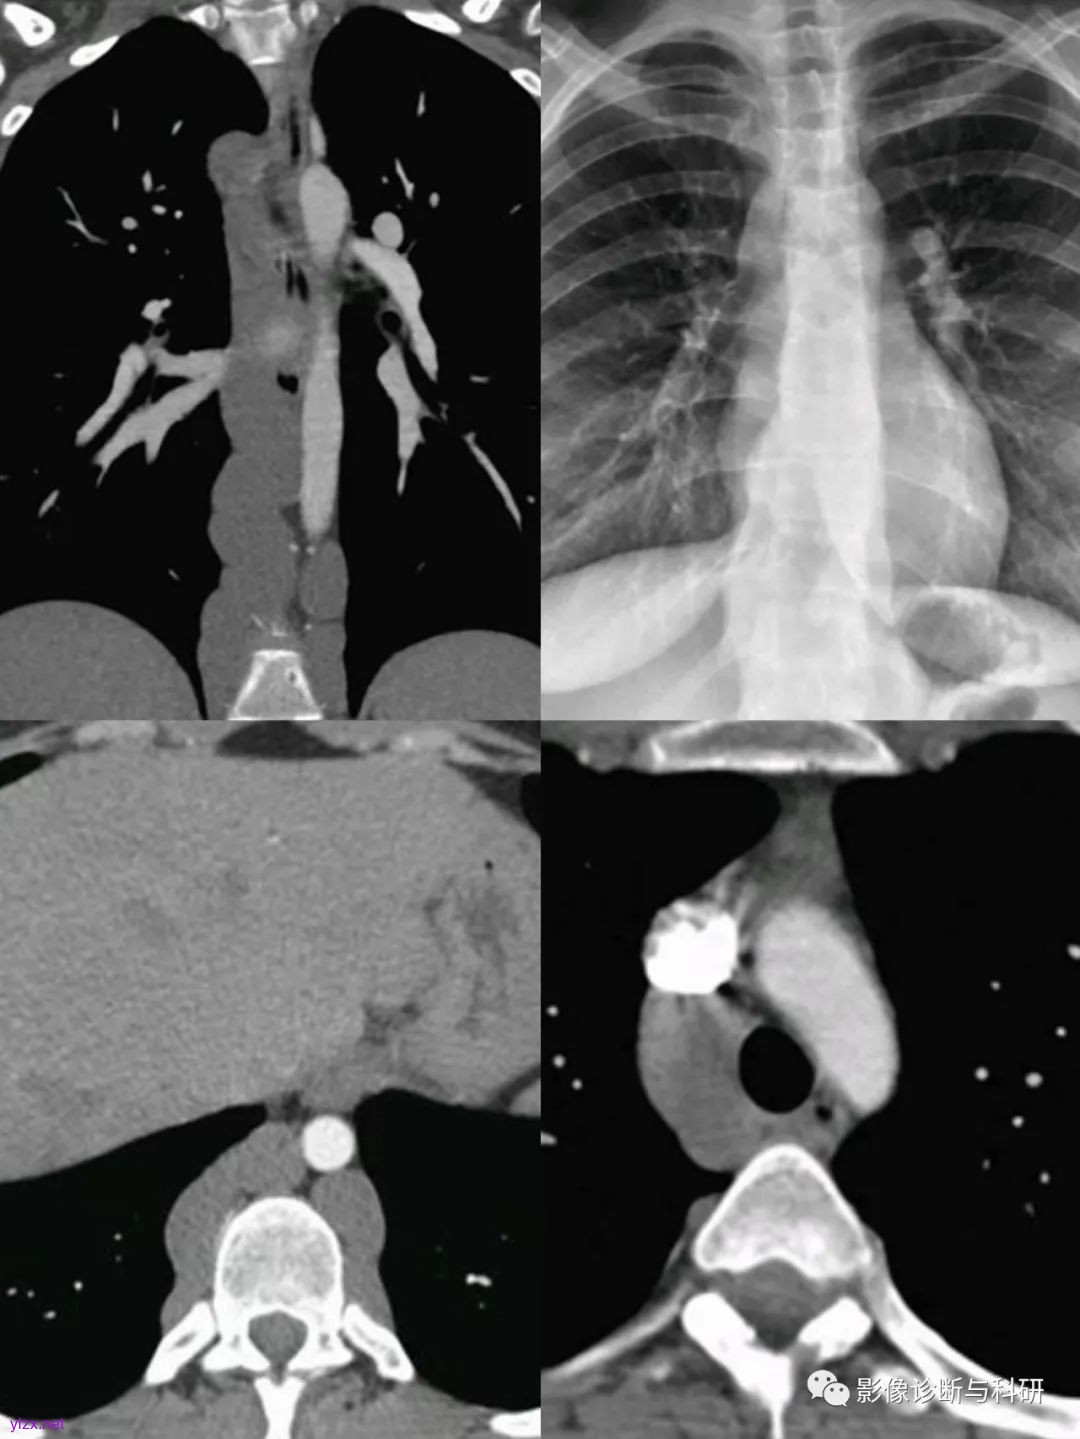

四、奇静脉扩张

引起奇静脉扩张的原因主要是两个方面:

一是患者的右心房压力突然增高。

当右房压力增高如肺动脉高压、主动脉夹层、动脉瘤、右心功能衰竭或大量心包积液时,右房的压力传导至上腔静脉及奇静脉,引起奇静脉压力增高,同时还阻碍静脉血回流至上、下腔静脉,奇静脉血流量增加,从而引起奇静脉扩张。

二是患者体内的奇静脉血流量增多。

当患者下腔静脉出现病变如下腔静脉栓子时,大量的静脉血通过奇静脉回流至上腔静脉,从而引起奇静脉扩张;当患者出现门静脉高压时,门体分流侧支循环开始建立,已经曲张的食管旁静脉与食管静脉会间接或者直接进入奇静脉,增加了患者奇静脉内部的血液流量,从而导致奇静脉扩张。另外奇静脉、半奇静脉与腰静脉、腰升静脉及左肾静脉都有交通支,因此当左肾静脉压迫或狭窄时,左肾静脉的血液可经这些交通支与奇静脉相连,从而使奇静脉压力增高且血流量增多。而先天性变异所导致的布加综合征患者形成一系列肝内及肝外侧支循环,其中有2条吻合支通过腰升静脉、奇静脉、半奇静脉系统,最终血液进入右心房,奇静脉成为最重要的侧支。